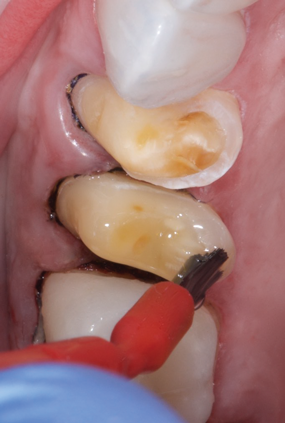

(3.) Prior to placing the restorations, the enamel of the abutment teeth is selectively etched with phosphoric acid for 20 seconds and a self-etch dentin primer is applied.

Figure 3

(4.) Prior to placing the restorations, the enamel of the abutment teeth is selectively etched with phosphoric acid for 20 seconds and a self-etch dentin primer is applied.

Figure 4